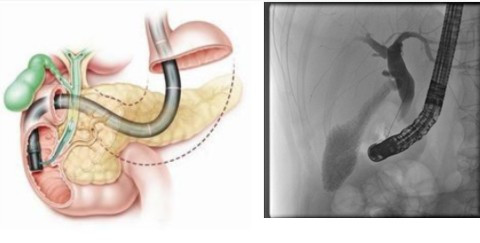

ERCP(消化介入)示意图。注:右侧图画收集自消化介入金规范移动C形臂——唯迈医疗Alien -E

所谓ERCP技能,是指经内镜逆行性胰胆管造影术(ERCP)是指将十二指肠镜插至十二指肠降部,找到十二指肠乳头,由活检管道内刺进造影导管至乳头开口部,注入造影剂后x线摄片,以显现胰胆管的介入技能。